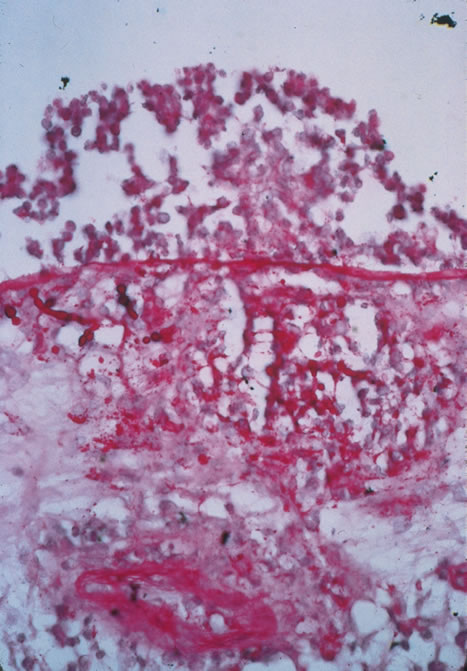

Pneumocystis carinii pneumonia once was the most common presentation of AIDS. It is typically of insidious onset, with features including dry cough, dyspnea, and a diffuse bilateral interstitial infiltrate evident on a chest roentgenogram. Typical multifocal fundus lesions have been described. They are yellow-white and have a characteristic pattern on fluorescein angiography (Fig. 10A, 10B, and 10C). Diagnosis is made by demonstrating the protozoon via sputum induction, bronchioalveolar lavage, and transbronchial or open-lung biopsies. Treatment modalities include trimethoprim-sulfamethoxazole (TMP-SMX).31

Fig. 10. A. The retinal involvement of Pneumocystis carinii is manifested by multifocal, yellow-white lesions. B and C. On fluorescein angiography, the lesions fail to delineate in the early phase (B) but stain in the late phase (C).